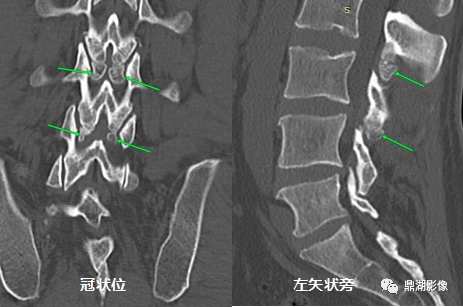

男性患者,40岁,腰背部疼痛,否认外伤史。

奥本海默小骨(Oppenheimer ossicle)

奥本海默小骨于 1942 年由Albert Oppenheimer首次描述,是关节突次级骨化中心不融合的结果。

好发于腰2和腰3椎体,主要表现为腰椎下关节突的游离小骨,也可发生于上关节突。通常无症状,多在影像学检查中偶然发现。

影像学特征:奥本海默小骨具有光整的骨皮质,相邻小关节的滑膜囊可与奥本海默小骨与关节突之间的裂隙相通。

在影像学上,需与关节突骨折相鉴别:奥本海默小骨形态规则、骨皮质光整、连续。